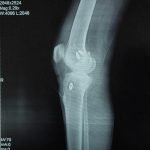

Orthopaedic Surgeon | Arthroscopy & Joint Replacement Specialist

- Robotic Joint Replacement

- Knee Replacement Surgery